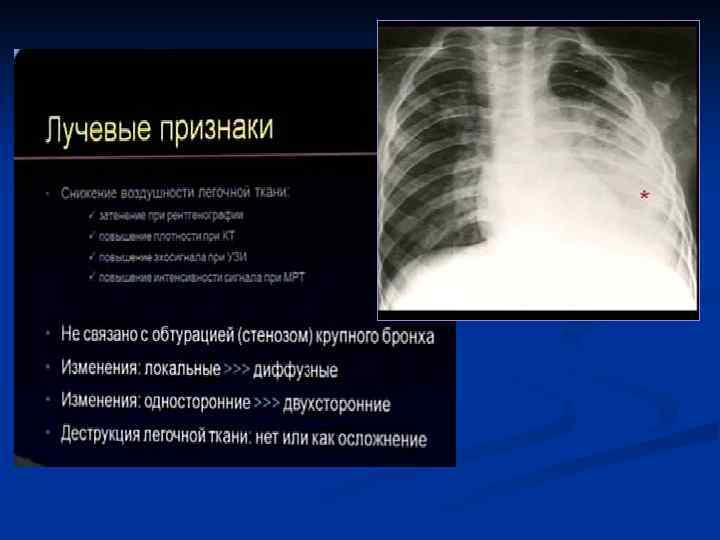

На I этапе обследования рентгенолог должен ответить на вопросы: Есть пневмония или нет 2. Локализация 3. Протяженность (если вся доля, то течение м. б. затяжное) 4. Характер пневмонии (долевой, ацинарный) 5. Первичная или вторичная На II этапе проследить изменения в динамике: 1. Рассасывание 2. Осложнения (нагноения, коллапсы) На III этапе (клинически выздоровление): 1. Полное ли рассасывание 2. Есть ли постпневмонические изменения легких (сетчатость, ячеистость) 1.

ИТАК, n Долевые и очаговые инфильтративные изменения обычно характерны для бактериальных пневмоний n Сетчатые интерстициальные изменения или сочетание инфильтративных и интерстициальных изменений типичны для пневмоний вирусной, микоплазменной, хламидийной и пневмоцистной природы, а милиарные поражения — для туберкулеза легких, генерализованного сальмонеллеза, грибковых поражений. n Инфильтративные или интерстициальные изменения в сочетании с лимфоаденопатией типичны для туберкулеза легких и пневмоний, вызванных грибами, микоплазмой, хламидиями, вирусами кори и ветряной оспы.